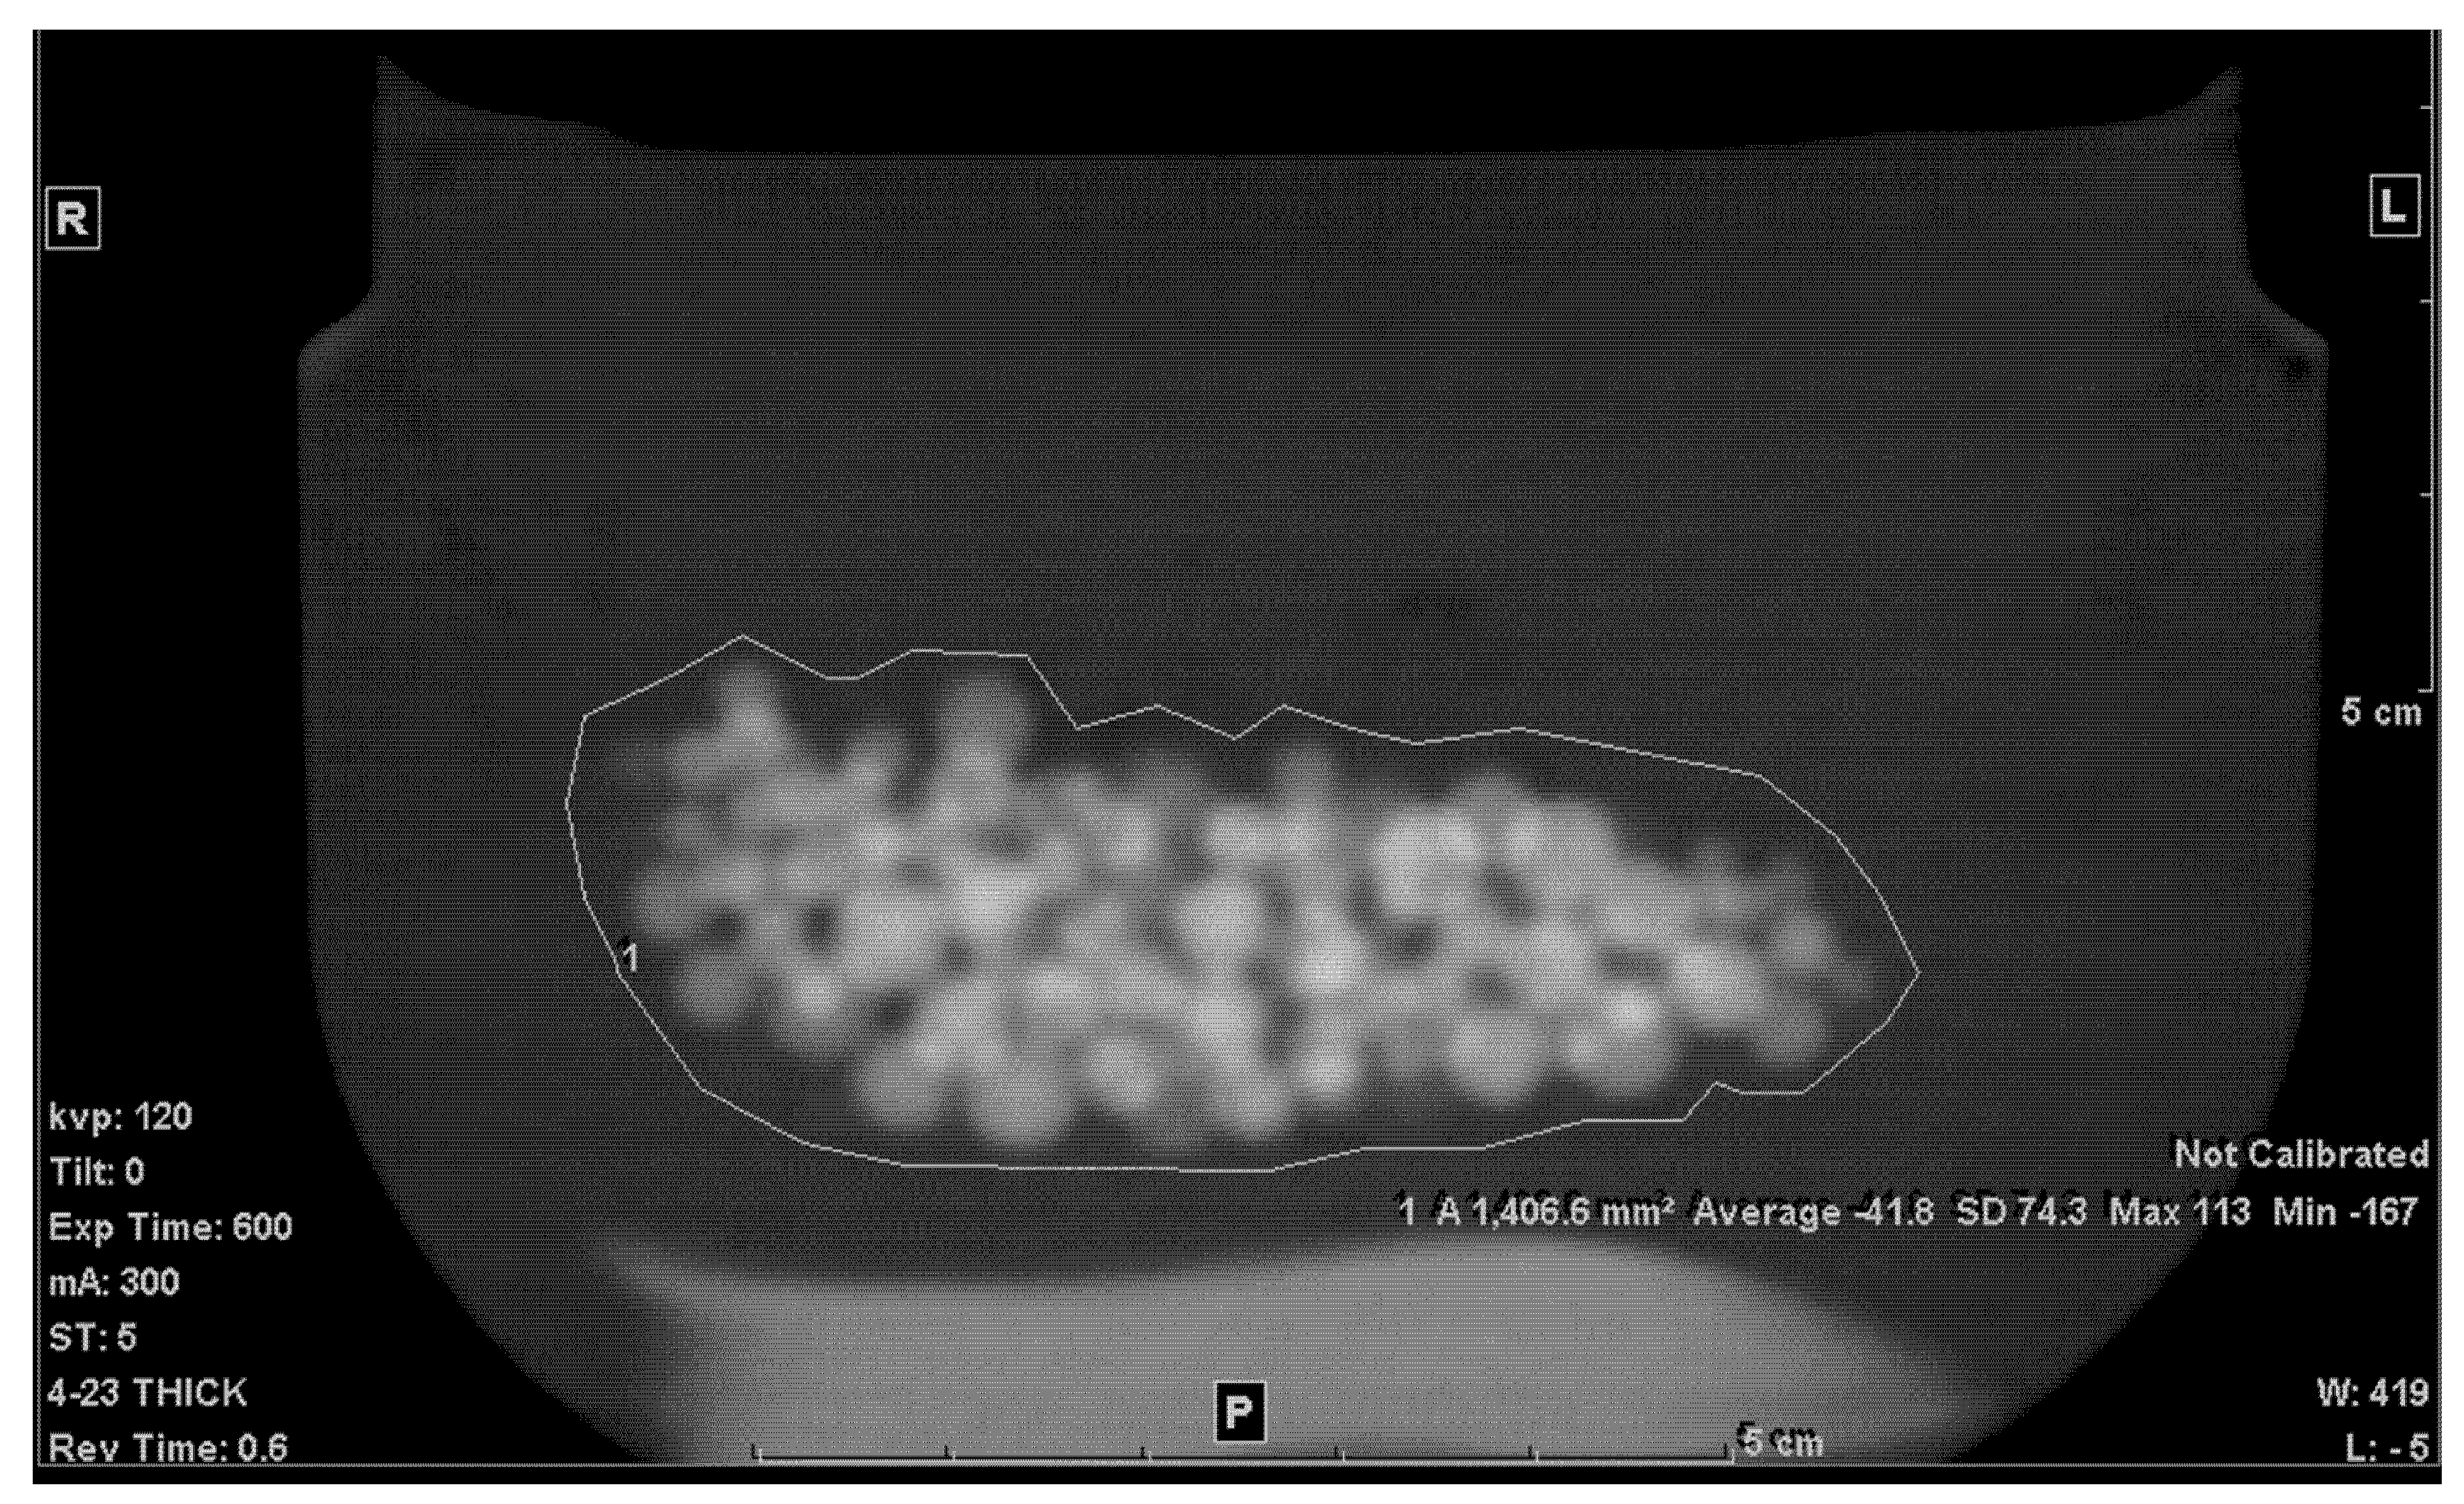

The second step was to draw an ROI in each of the slices that included any portion of the beads. A freehand ROI drawing option was used to ensure that no other pixels other than the jelly and the beads were included, as seen in Figure 2. For each slice, the mean density in Hounsfield units (HU), standard deviation (SD), and the area of the ROI in mm2 were shown on the workstation image. Both the mean density and area were recorded.

Figure 2.

Freehand ROI of the mixture on a 5 mm-thick slice.